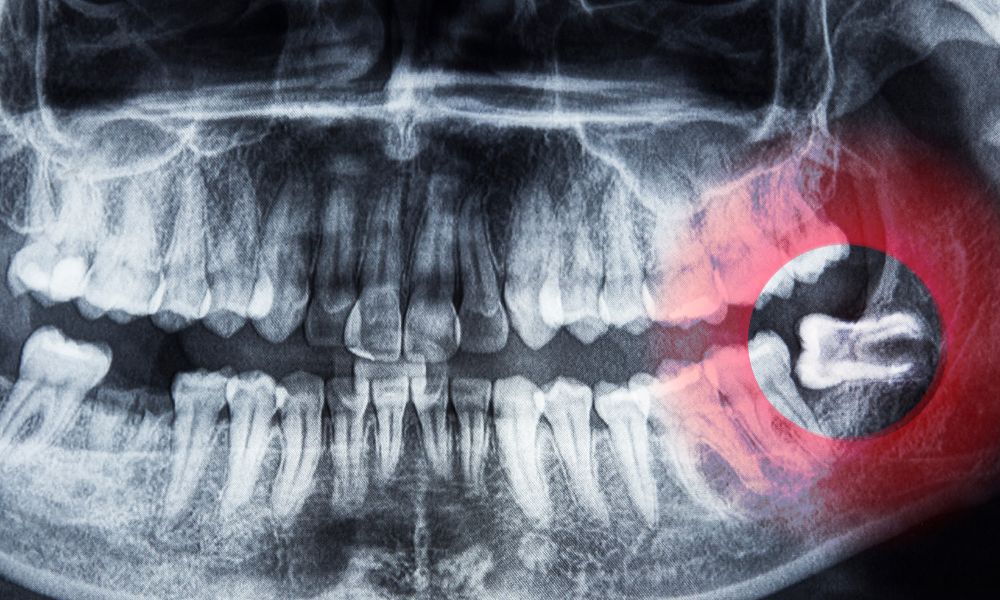

Proceso de erupción de las muelas del juicio

La salida de estas muelas puede causar dolor e inflamación. Algunas crecen en ángulos incorrectos o se quedan dentro del maxilar. Esto puede provocar infecciones, caries o quistes en la mandíbula.

La erupción de las muelas del juicio puede causar problemas cuando no hay espacio suficiente. La American Dental Association sugiere considerar la cirugía si hay dolor en estas piezas. Veamos algunos problemas frecuentes relacionados con las muelas del juicio.

Falta de espacio en la cavidad bucal

Las muelas del juicio pueden quedarse atrapadas en la mandíbula sin espacio suficiente. Esto puede provocar infecciones o quistes que dañan otros dientes y el hueso. La cirugía puede ser necesaria para prevenir daños y mantener una buena salud bucal.

Infecciones y pericoronaritis

Las muelas del juicio que emergen parcialmente pueden causar infecciones en las encías. La pericoronaritis es una infección común que inflama el tejido alrededor del diente retenido.

Si no se trata, la infección puede extenderse y causar complicaciones graves. Es importante atender estos problemas a tiempo.